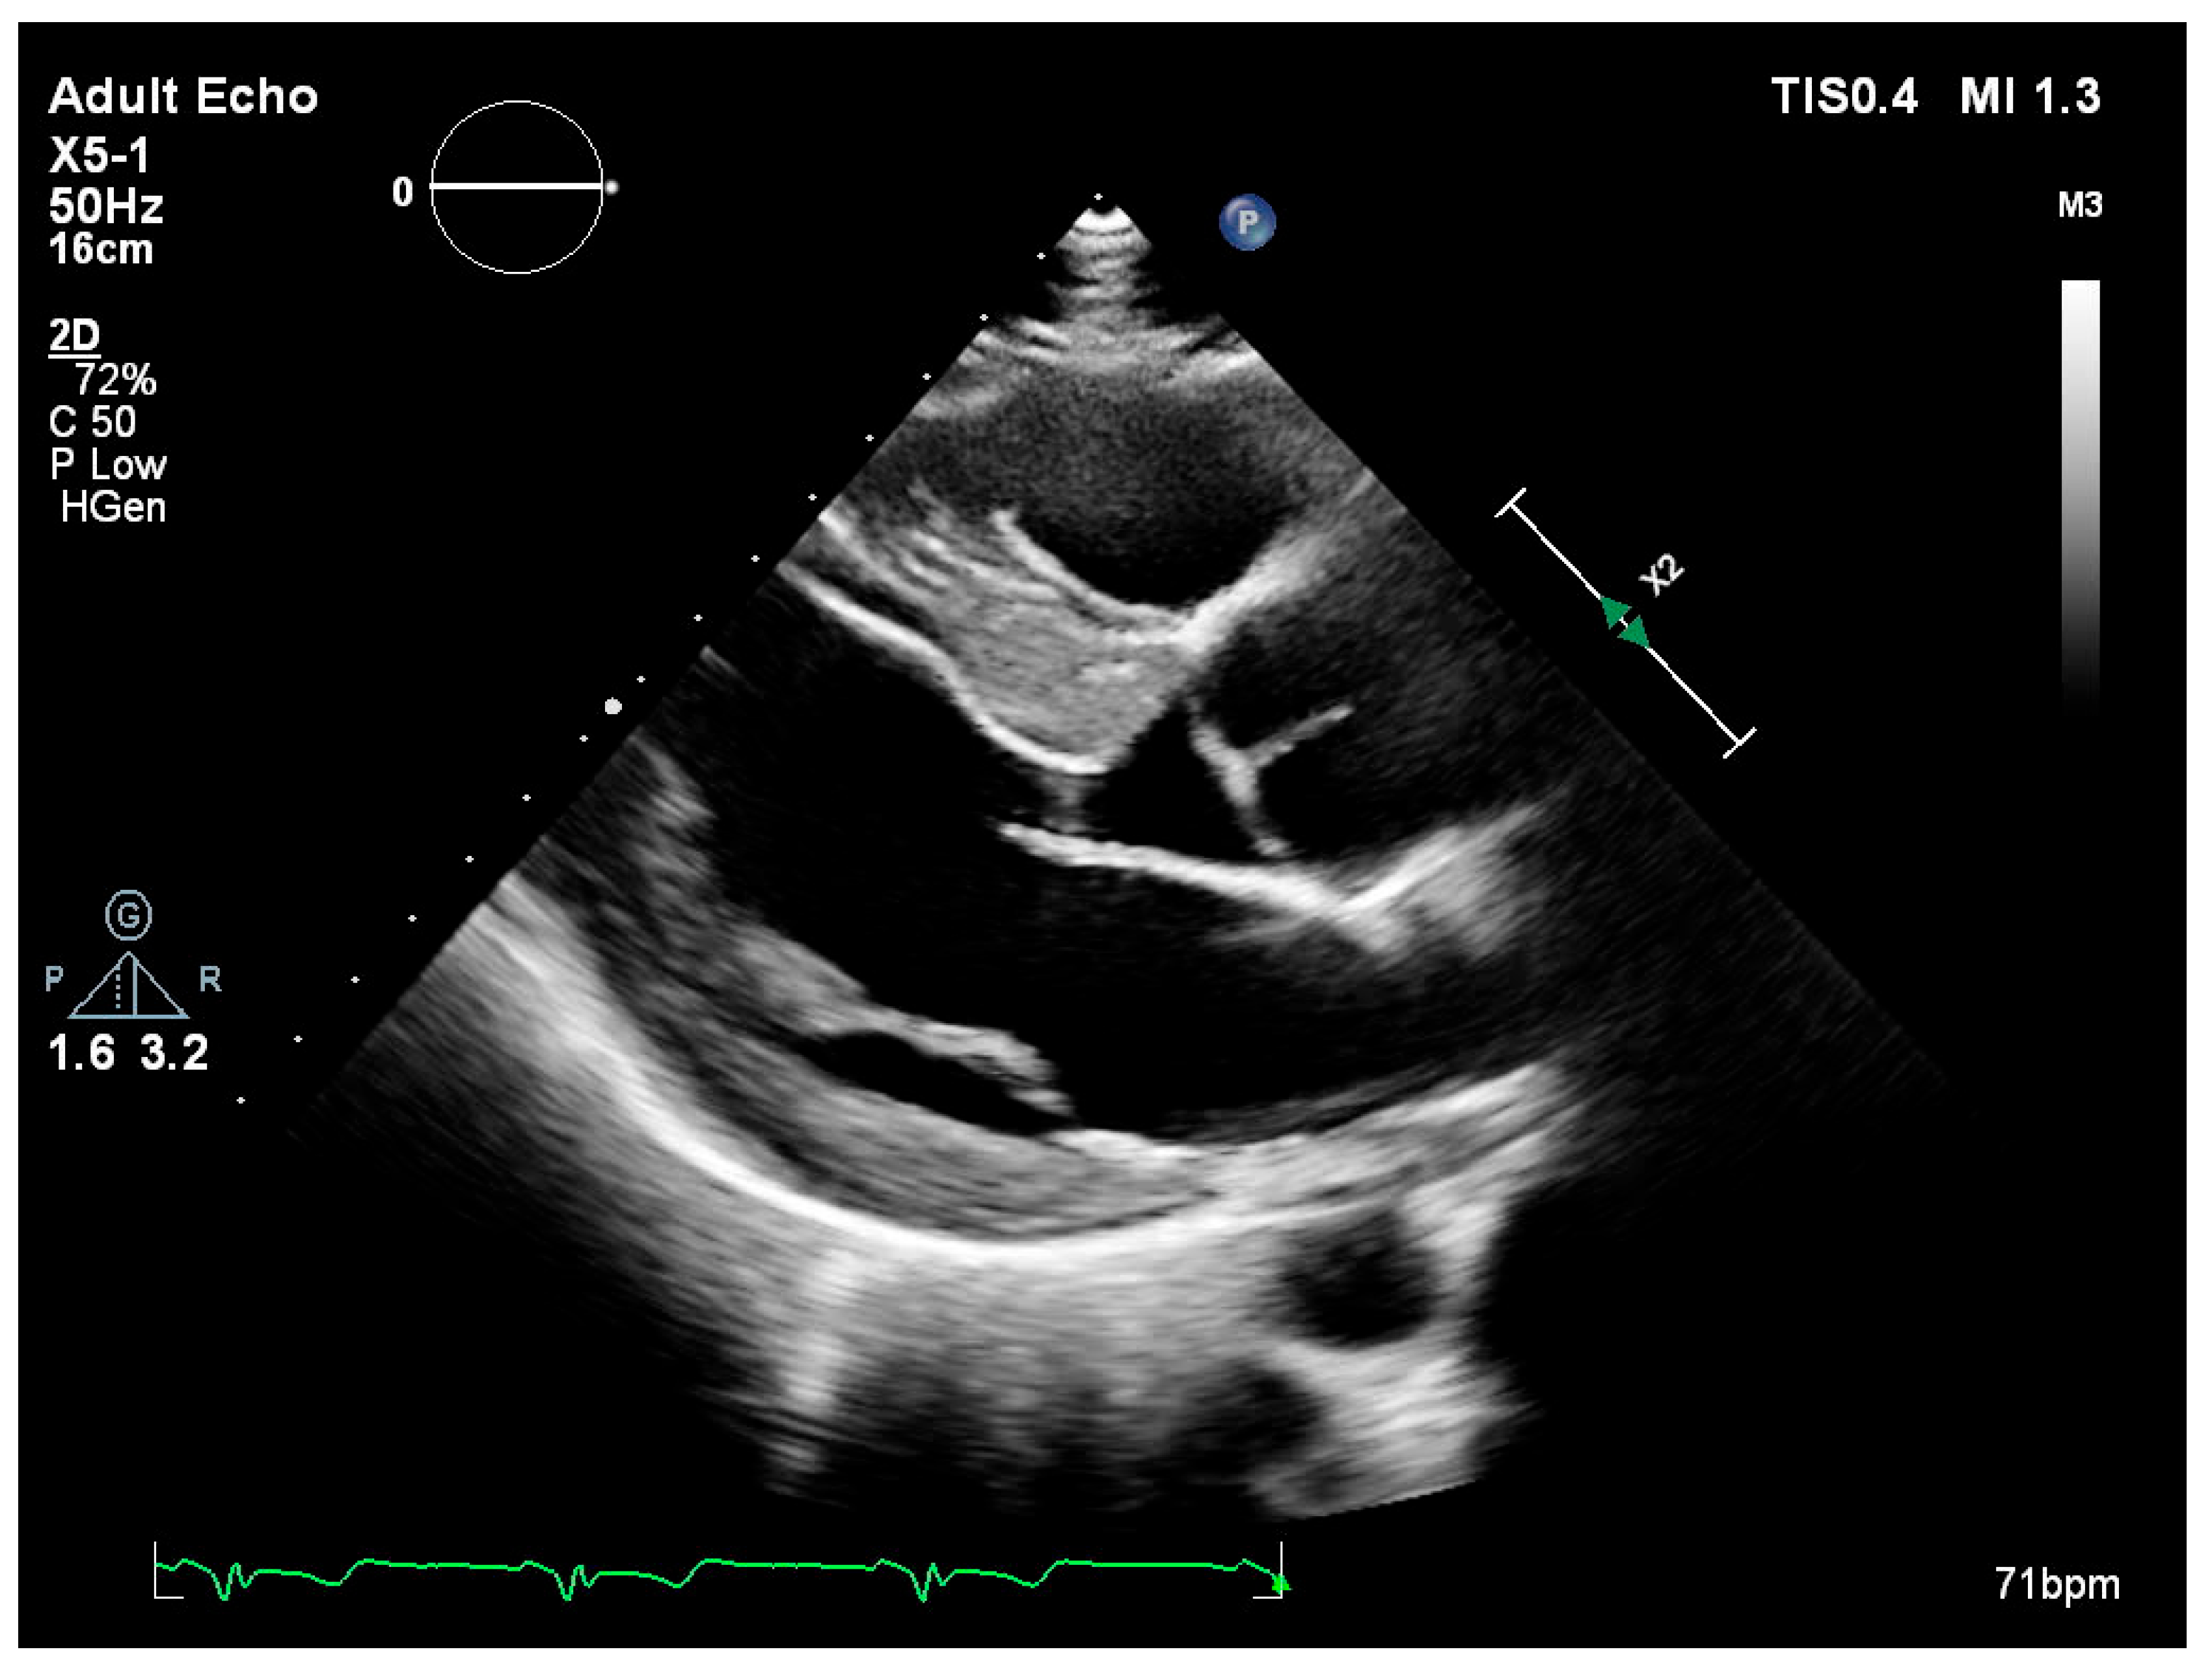

Left ventricular internal diameters in systole (LVIDs) and diastole (LVIDd) were slightly lower in FD patients compared to the non-FD group [LVIDs: 45.5 mm (36.0–49.0) vs. 47.0 mm (42.0–52.0); LVIDd: 28.0 mm (24.5–31.5) vs. 30.5 mm (25.3–37.0)] (Table 3). Measurements of wall thickness showed similar trends, with FD patients exhibiting slightly lower values in both posterior wall and interventricular septum thickness during systole and diastole. Notably, the median interventricular septum thickness in diastole (IVSd) was 15.5 mm (IQR: 15.0–16.0) in FD patients compared to 18.0 mm (IQR: 16.0–22.5) in the non-FD group (Table 3). Left ventricular ejection fraction (EF) was preserved in both groups, with a higher median value observed in FD patients [65.0% (65.0–65.0) vs. 60.0% (55.0–65.0)]. Right ventricular function as measured by TAPSE was also slightly higher in FD patients [25.0 mm (25.0–30.0)] versus non-FD patients [23.0 mm (20.0–28.0)] (Table 3). There were no marked differences in left atrial and right atrial dimensions or filling pressures between groups. The E/A ratio and E/E′ values in FD patients were within the expected range and comparable to non-FD patients (Table 3). Figure 1 (parasternal long-axis) and Figure 2 (apical four-chamber) present concentric left ventricular hypertrophy consistent with hypertrophic cardiomyopathy in a patient with genetically confirmed Fabry disease (own clinical material).

Figure 1. Transthoracic echocardiography—parasternal long-axis view showing severe left ventricular hypertrophy.